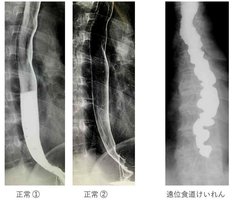

食道の動きはバリウムを用いた上部消化管レントゲン造影検査で見ると、正常であれば写真の「正常①」のようにバリウムを飲んだ直後のバリウムは白く写っていますが、蠕動運動によって「正常②」ではバリウムはすぐに食道から胃内に移動します。しかし、典型的な遠位食道けいれんの患者さんは、食道内に白く写るバリウムが長時間にわたりとどまっています(写真右)。食道壁が、神経障害によって収縮と拡張を同時に出現させるため、蠕動運動は正常に行われません。平滑筋である食道の下3分の2の食道壁に凹凸があって「けいれん」しているように見えるため「遠位食道けいれん」と呼ばれます。